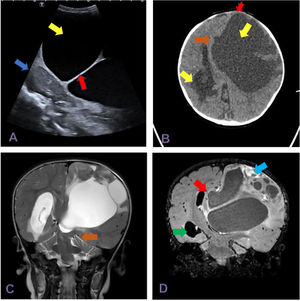

The transfontanellar ultrasound examination revealed a voluminous anechoic multiseptated lesion with contralateral midline shift (Fig. 1A). This finding prompted additional imaging of the brain with CT and MRI (Fig. 1B–D). These tests allowed visualization of a hypodense multiseptated lesion in the left frontoparietal region with a mass effect on the left lateral ventricle resulting in midline shift and the obliteration of the suprasellar and perimesencephalic cisterns with signs of subfalcine and descending transtentorial herniation.

(A) Transfontanellar ultrasound with a 5–8MHzmicro-convex array transducer (sagittal plane) showing an anechoic lesion (yellow arrow), multiseptated (red arrow), with a cystic appearance, compressing the adjacent cerebellar parenchyma (blue arrow). (B) CT scan, axial view, showing a supratentorial multiseptated lesion with a large cystic component (yellow arrow). It exerted a mass effect on the metopic suture, which was bulging (red arrow), with midline shift (brown arrow), dilatation of the temporal and occipital horns of the right lateral ventricle (green arrow) and transependymal oedema secondary to hydrocephalus. (C) T2-weighted MRI of the brainstem, coronal plane, evincing descending transtentorial herniation (brown arrow). (D) Gadolinium-enhanced FLAIR MRI of the brainstem, coronal plane, showing a large cystic lesion with an enhanced peripheral solid component (blue arrow), midline shift (brown arrow) and ventricular dilatation with transependymal oedema (green arrow).